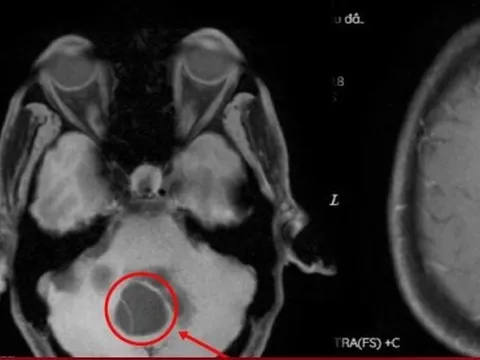

Ứng dụng kỹ thuật cao cứu ca bệnh u thần kinh méo mặt, liệt chân

(NLĐO - Kỹ thuật cao này đòi hỏi bác sĩ luôn theo sát người bệnh cả trước, trong và sau mổ trong suốt quá trình điều trị.